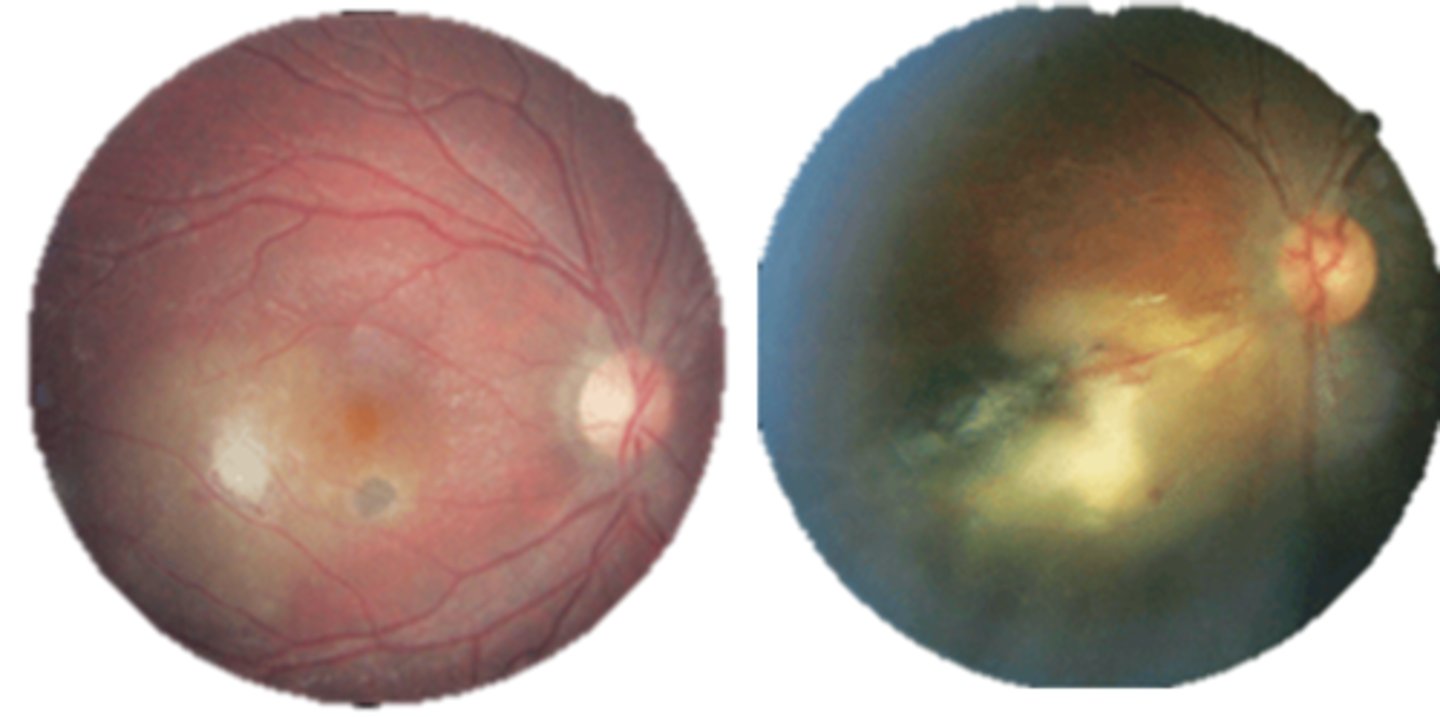

What findings of toxoplasmosis are seen here?

retinal vasculitis

exudative scar

focal, hazy vitritis and retinitis